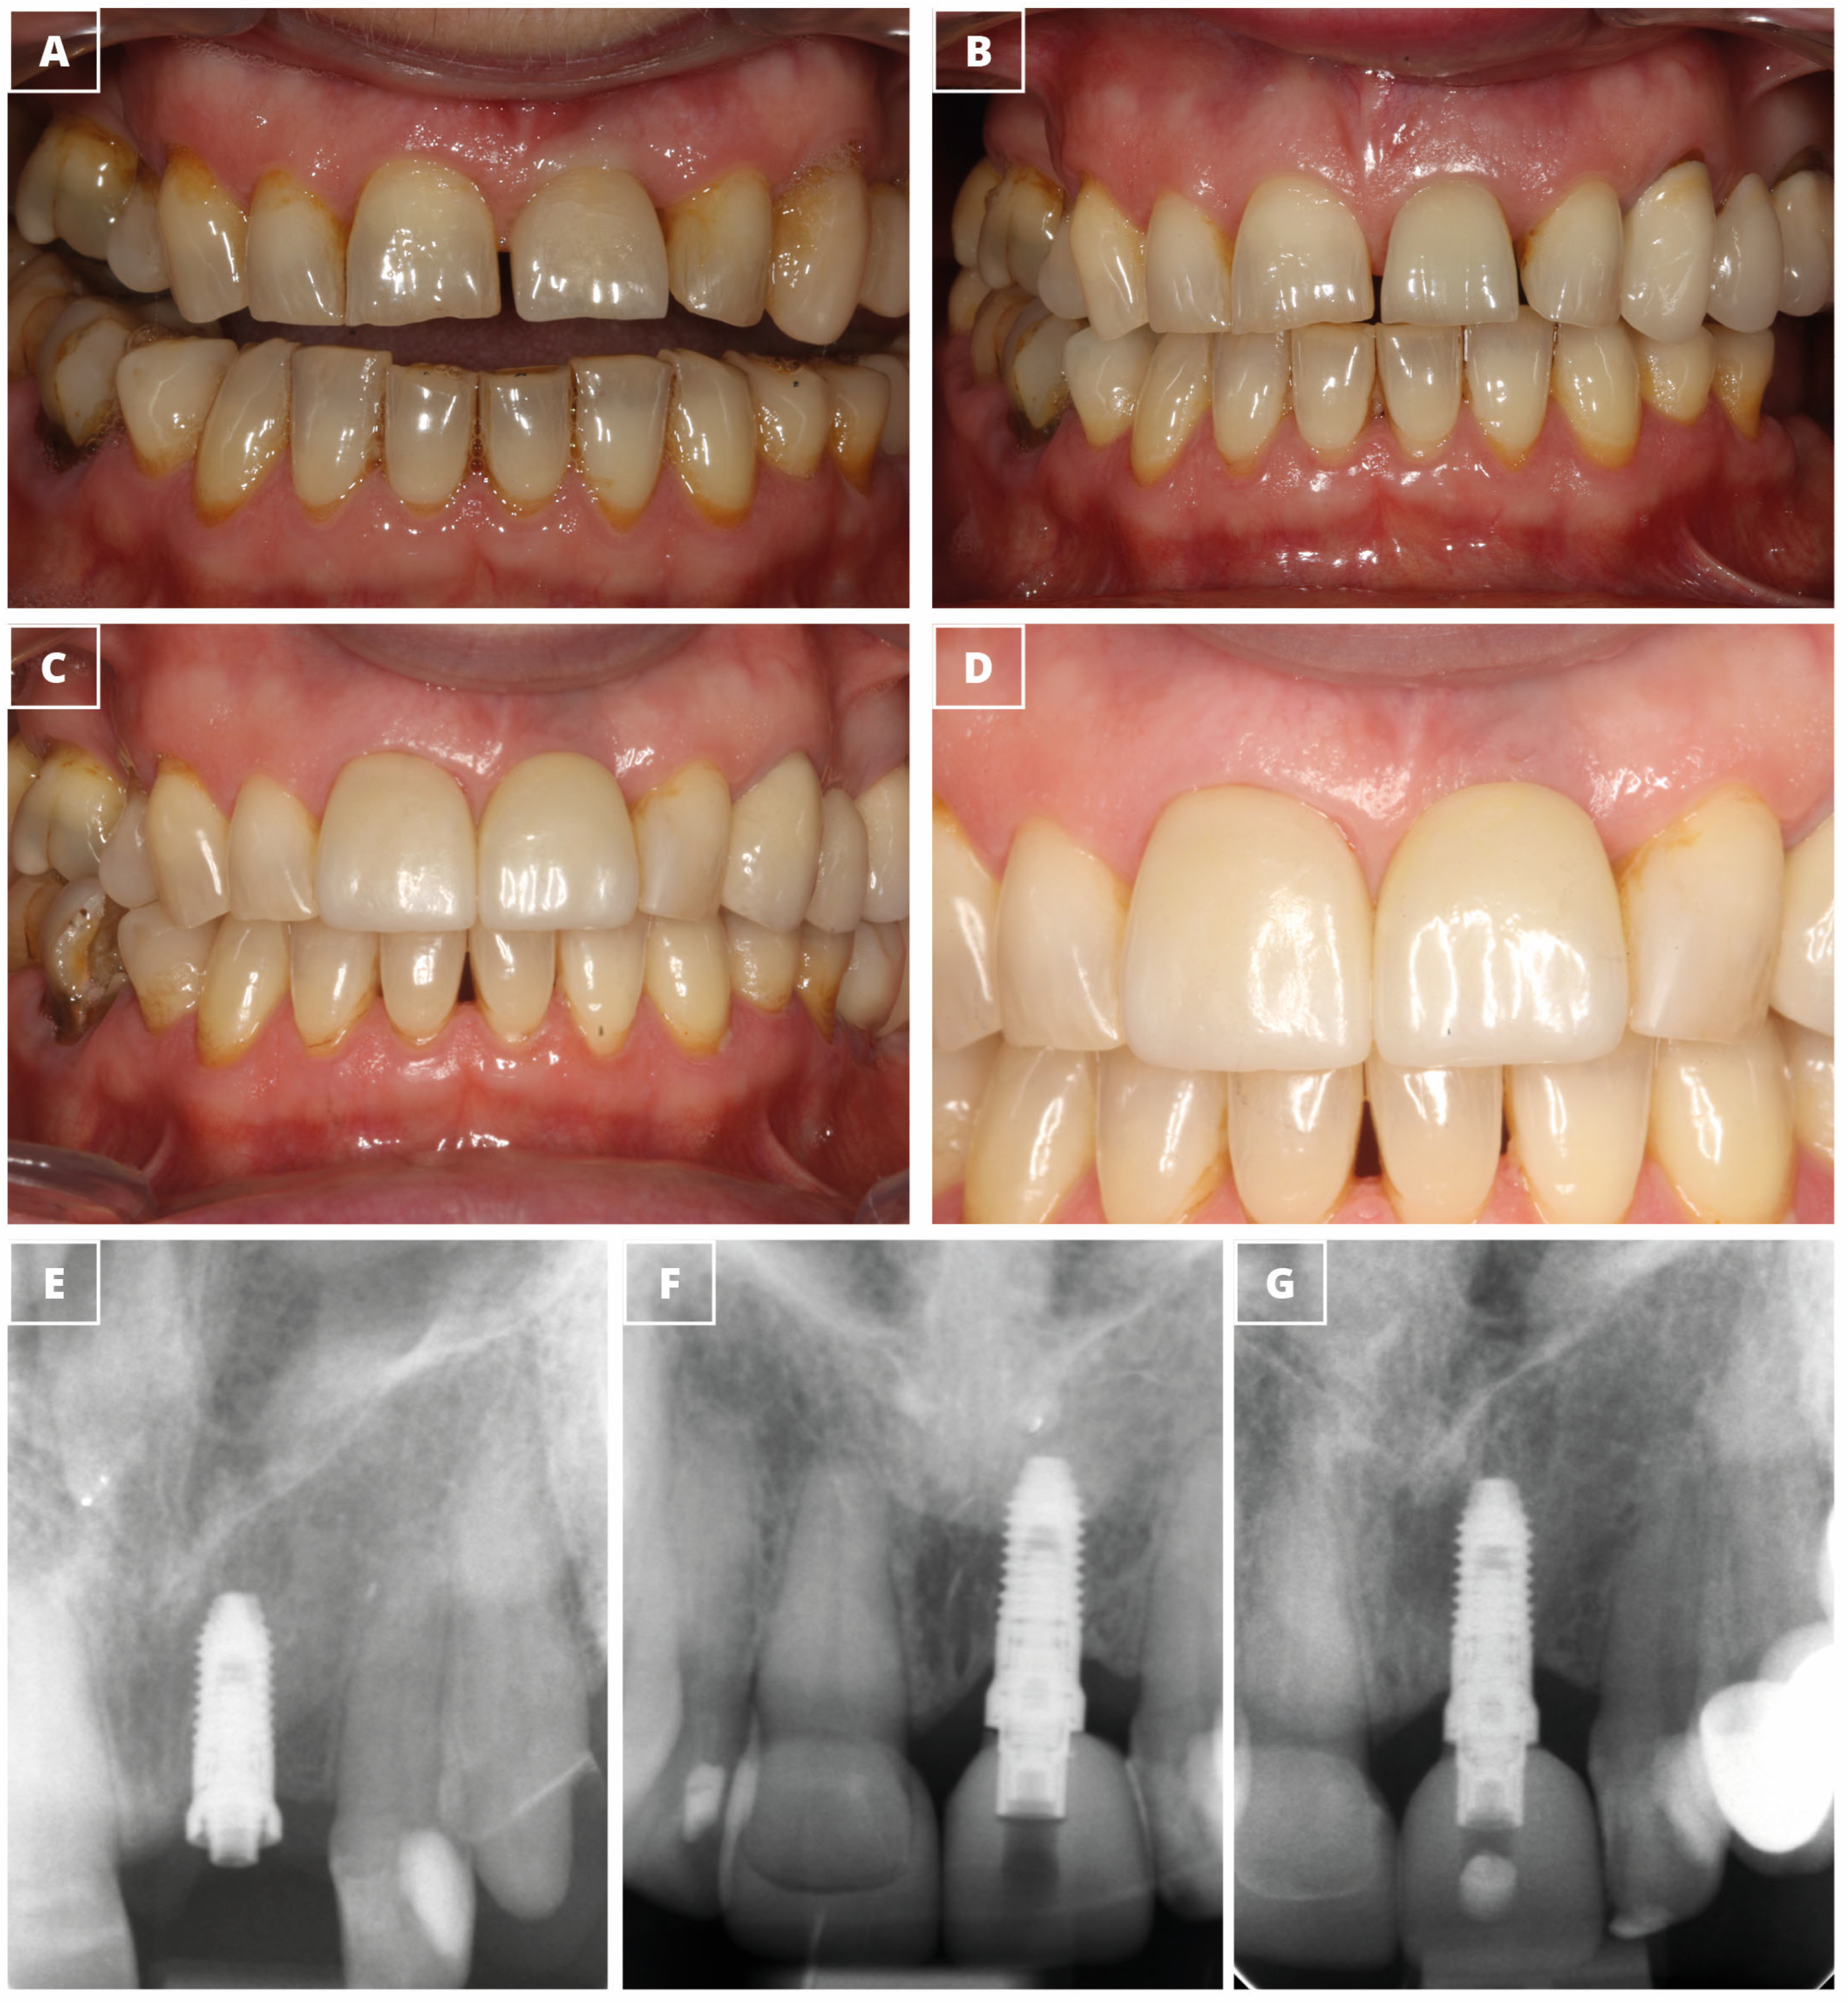

| Pink Esthetic Score | 7.0 ± 2.6 | |

| White Esthetic Score | 7.9 ± 2.0 |